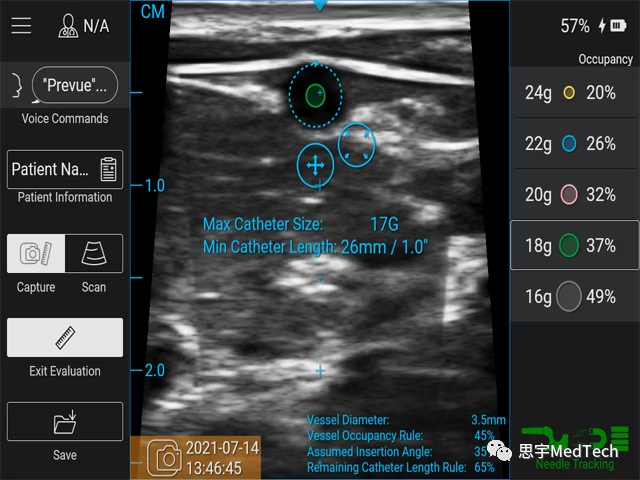

Prevue™ II系统具有创新的血管评估工具,可以帮助临床医生根据插入位置和角度来选择合适的导管长度和规格。